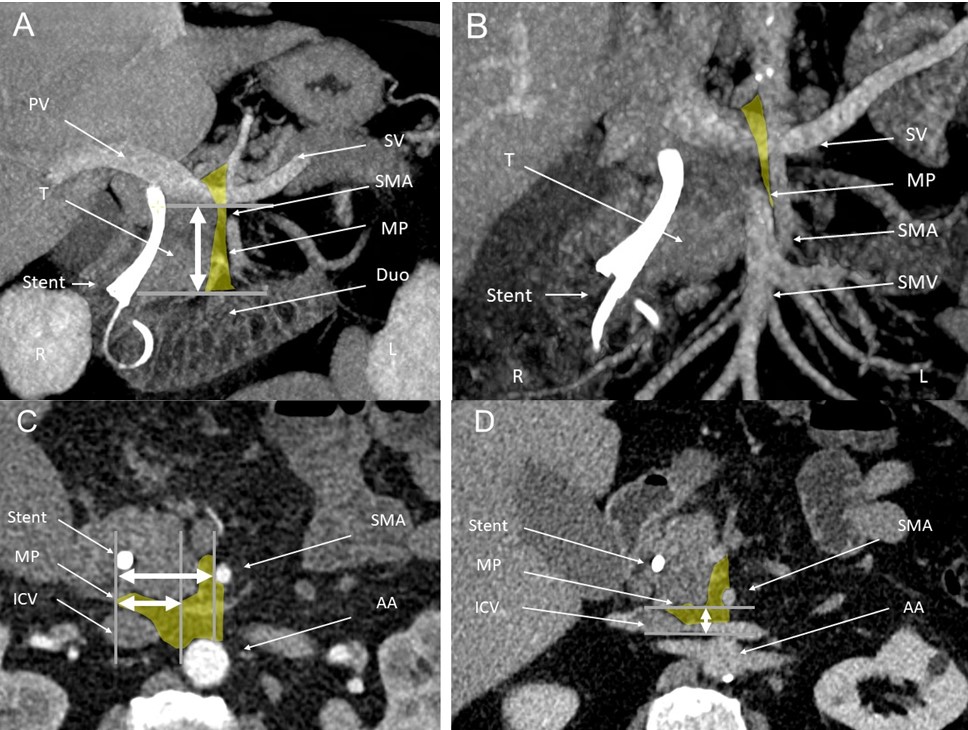

KV 127 Skelettmuskelmasse als Prädiktor für das Ansprechen auf Terlipressin bei der Behandlung des Hepatorenalen Syndroms

S. Oesinghaus1, J. Pohl1, T. Villar de Rhode1, N. Beetz2, D. Geisel2, F. Tacke1, C. Engelmann1

1Charité Campus Virchow und Campus Mitte – Universitätsmedizin Berlin, Klinik für Innere Medizin m.d.S. für Gastroenterologie und Hepatologie, Berlin, Deutschland, 2Charité – Universitätsmedizin Berlin, Klinik für Radiologie, Berlin, Deutschland

Einleitung: Das Hepatorenale Syndrom (HRS) ist eine schwere Form des akuten Nierenversagens bei Leberzirrhose und geht unbehandelt mit einer hohen Kurzzeit-Mortalität einher. Terlipressin in Kombination mit Albumin stellt die Standardtherapie dar. Die KI-gestützte CT-Body Composition Analyse (BCA) hat sich als vielversprechender Ansatz zur Risikostratifizierung bei Leberzirrhose etabliert, wodurch sie das Potenzial zur frühzeitigen Identifikation vulnerabler Patient:innengruppen bietet.

Ziele: Ziel der Studie ist es, prognostische Faktoren für das transplantationsfreie Überleben zu untersuchen und mithilfe der BCA prädiktive Marker für das Terlipressinansprechen zu identifizieren.

Methodik: Retrospektiv wurden 121 Patient:innen mit HRS eingeschlossen, die zwischen 2018 und 2022 eine Terlipressintherapie erhielten. Das Therapieansprechen wurde nach 14 Tagen anhand dreier Definitionen evaluiert: (1) Rückgang des Serumkreatinins auf ±0,3 mg/dl des Ausgangswerts, (2) Reduktion des Peak-Serumkreatinins um ≥25 %, (3) Verbesserung der Nierenfunktion um ≥1 ANV-Stadium. Anhand der BCA wurde die Muskelfläche auf L3-Höhe erhoben, indexiert [cm²/m²] und der Skelettmuskelindex (SMI) berechnet. Regressions- und Competing-Risk-Analysen identifizierten unabhängige Prädiktoren für das Terlipressinansprechen und das transplantationsfreie Überleben nach 12 Monaten.

Ergebnis: Der mittlere SMI betrug bei Männern 39,2 ± 8,7 cm²/m² und bei Frauen 35,9 ± 6,0 cm²/m². Nach 12 Monaten waren 66 der 121 Patient:innen (54,5 %) verstorben und 6 (5,0 %) lebertransplantiert. Das Terlipressinansprechen betrug 29,8 %, 45,5 % bzw. 47,1 % entspr. der Definitionen 1–3. In der Competing-Risk-Analyse war ein Therapieansprechen gem. aller drei Definitionen mit einem signifikant besseren transplantationsfreien Überleben nach 12 Monaten assoziiert. Ein Abfall des Peak-Serumkreatinins um mindestens 25% bis Tag 14 erwies sich hierbei als stärkster Prädiktor (HR 0,25; KI-95% 0,14-0,42; p < 0,0001). In den multivariaten COX-Modellen war ein niedriger SMI ein robuster unabhängiger Prädiktor für ein fehlendes Terlipressinansprechen gem. Definition (2) (HR 1,95; KI-95% 1,24-3,07; p < 0,01).

Schlussfolgerung: Die Muskelmasse, gemessen am SMI, ist ein unabhängiger Prädiktor für das Ansprechen auf Terlipressin bei der Behandlung des HRS. Größere multizentrische Studien sind jedoch notwendig, um Patient:innen mit unzureichendem Therapieansprechen anhand dessen zu identifizieren.

09:18 – 09:24